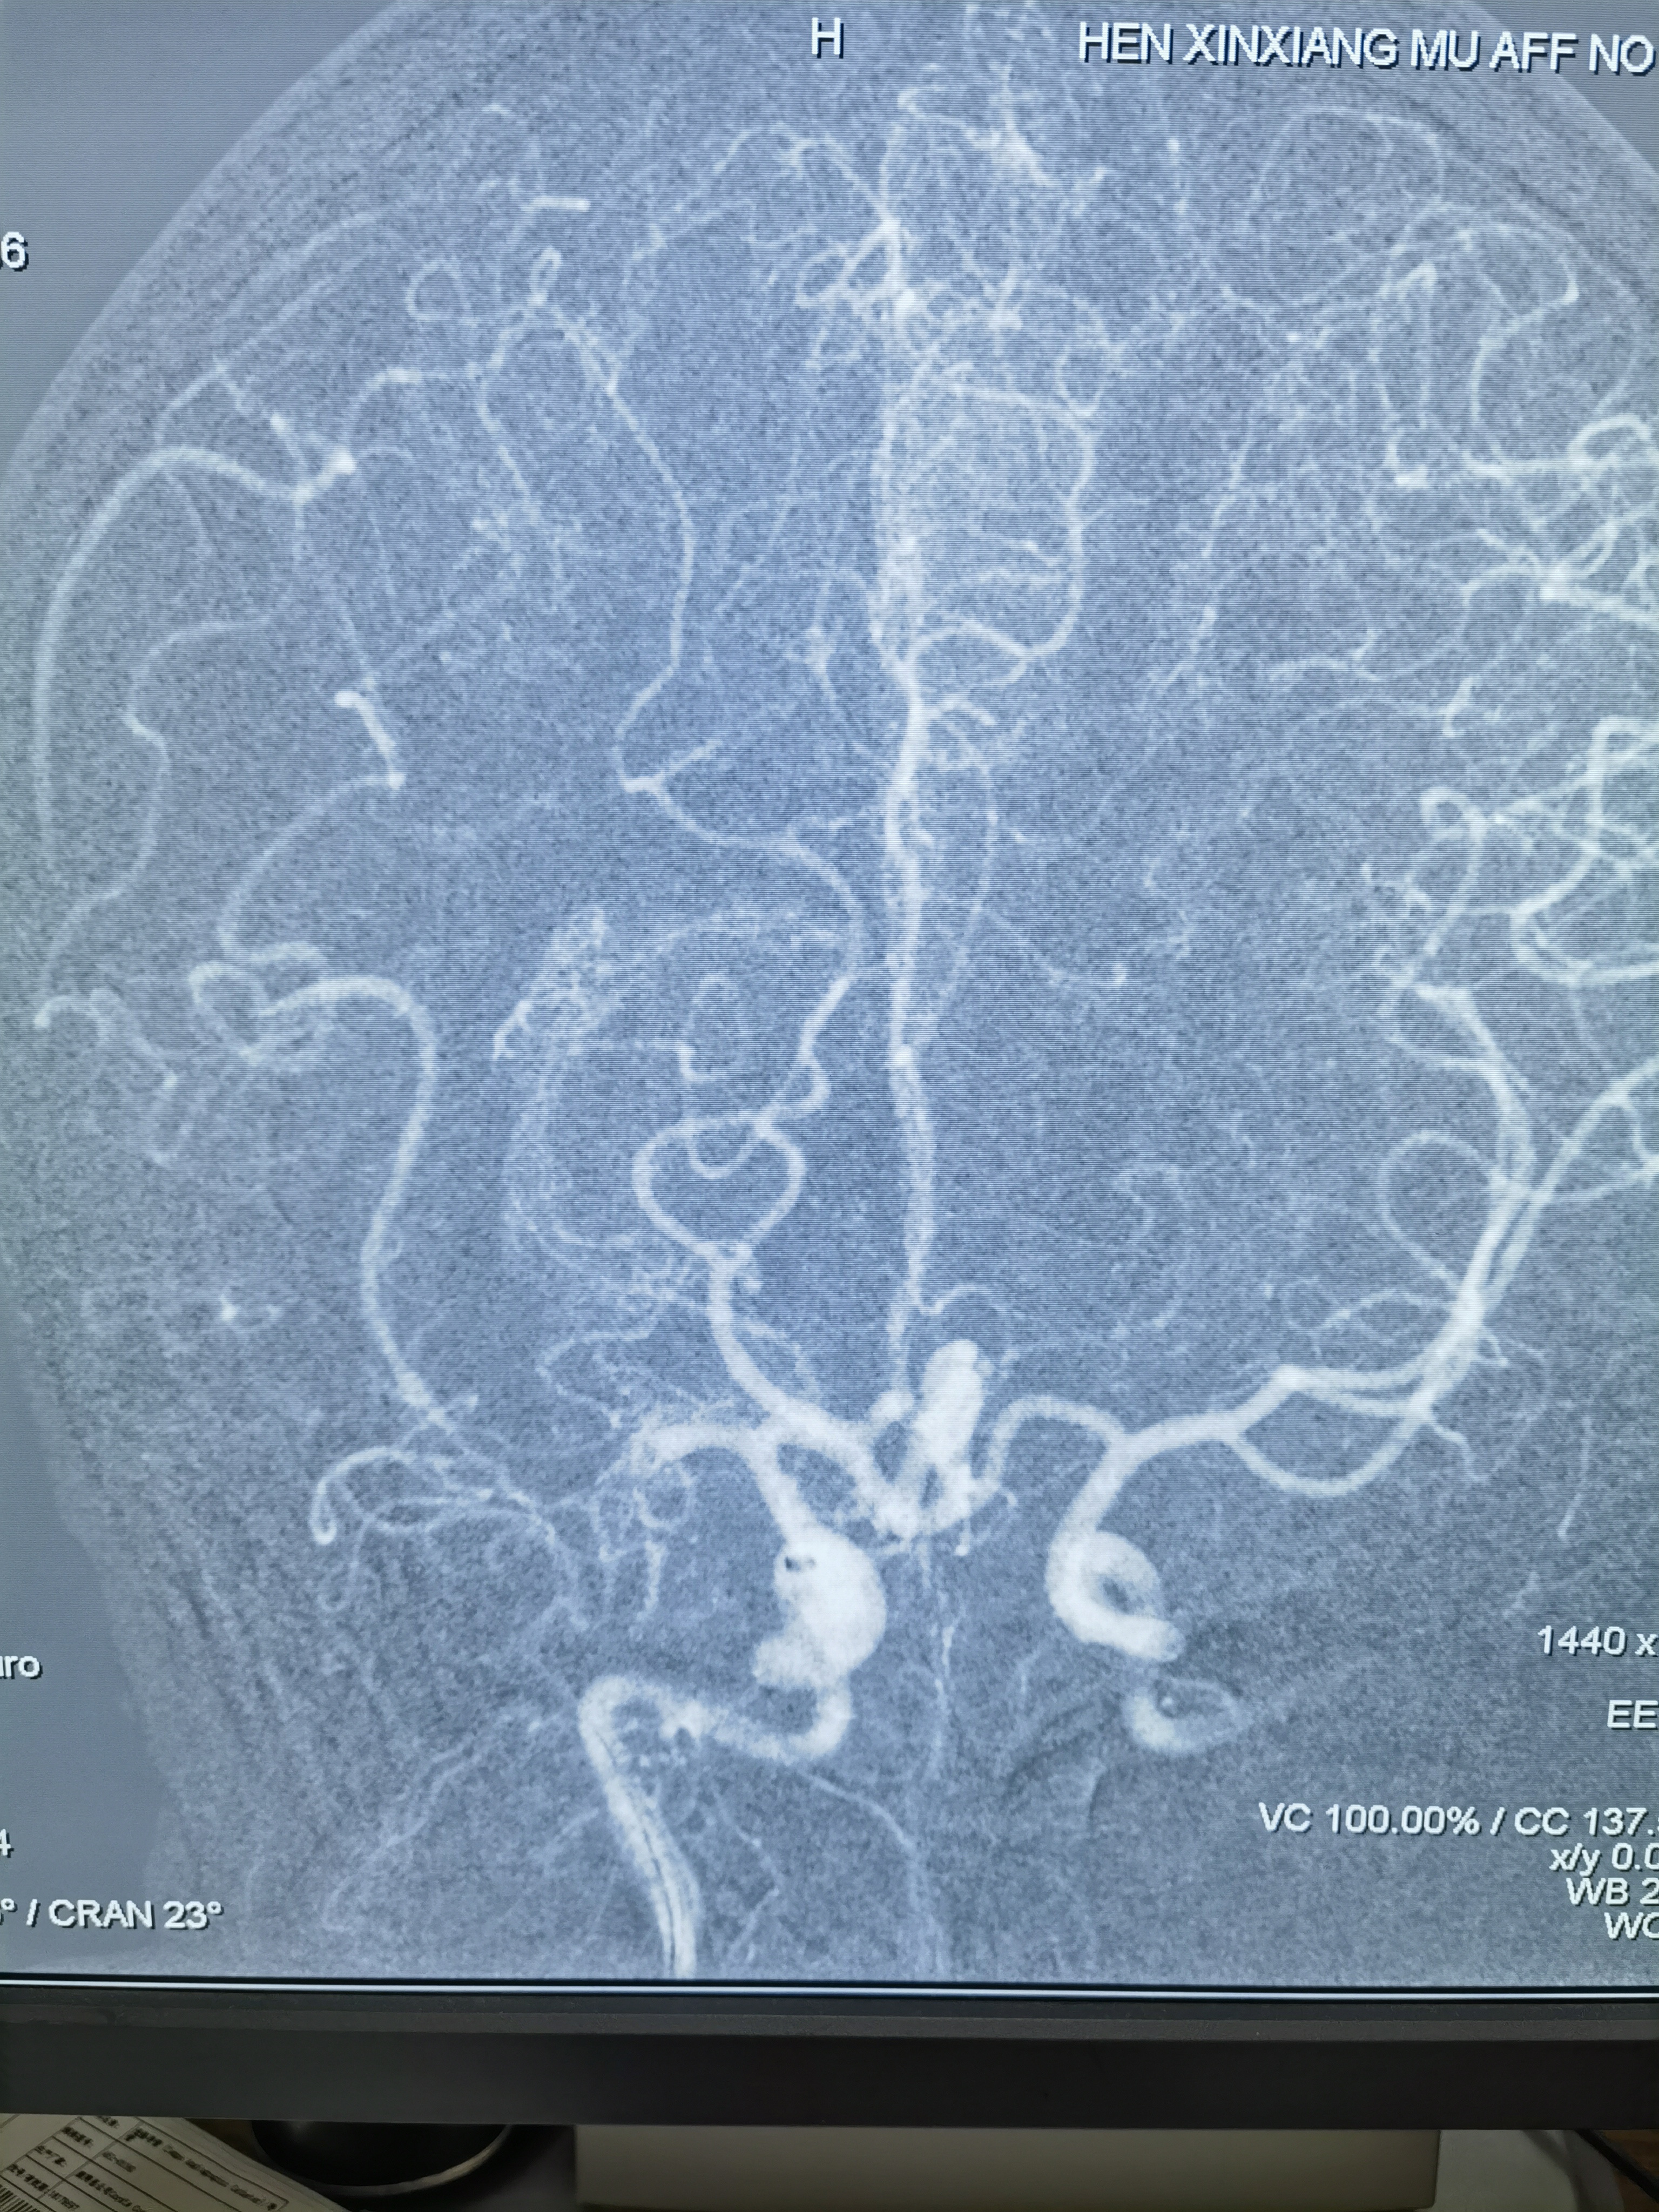

扩完血流恢复,血管通了,但是大脑中动脉M1仍有血栓,似乎还有点夹层,动脉给了10ml替罗非斑,观十余分钟,M1血栓又增加了,血流也变差,怎么办?想支架成型,但是患者有大动脉炎,不贴支架血流维持不住,术中商量一下考虑患者年轻,还是要尽量让患者降低瘫痪的机率,遂决定植入药物涂层支架,就算动脉炎引起支架内闭塞也需要一定时间,患者大脑前有通过软膜支向大脑中供血区代偿,到时候慢性闭塞可能患者不会出现严重影响!

药物涂层支架

支架植入后血流完成恢复!